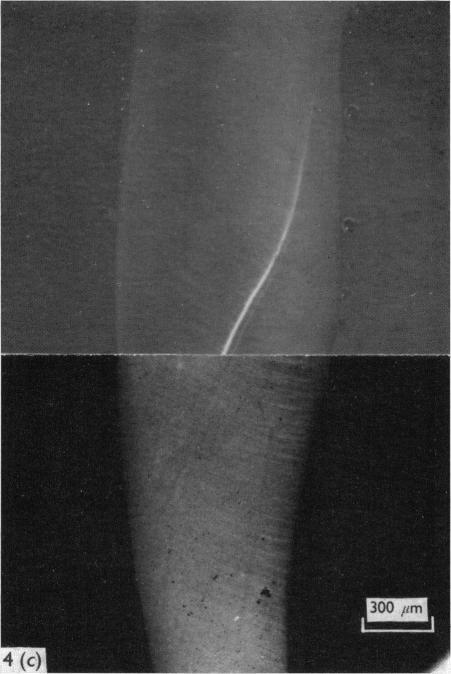

Ground and decalcified sections of human, goat and pig teeth were examined using polarized and ultraviolet fluorescence microscopy, microradiography and electron microscopy. The experimental animals were given doses of tetracycline within the range 3-150 mg/kg. After the low doses there was no evidence of any disturbance of mineralization or of structural organization in either the goat or the pig. After the higher doses, however, the tetracycline lines usually corresponded with a disturbance of structural organization and often with a disturbance of mineralization as well. In the human cases, the tetracycline lines sometimes corresponded with a disturbance of mineralization or of structural organization. However, our evidence suggests that the disturbances in the structure or mineralization of the dentine in the human subjects were not caused by the tetracycline. It was concluded that, provided the dose is kept low (3-31 mg/kg) tetracycline can be used as a reliable non-toxic marker in growth studies and is also used in the study of mineral deposition.